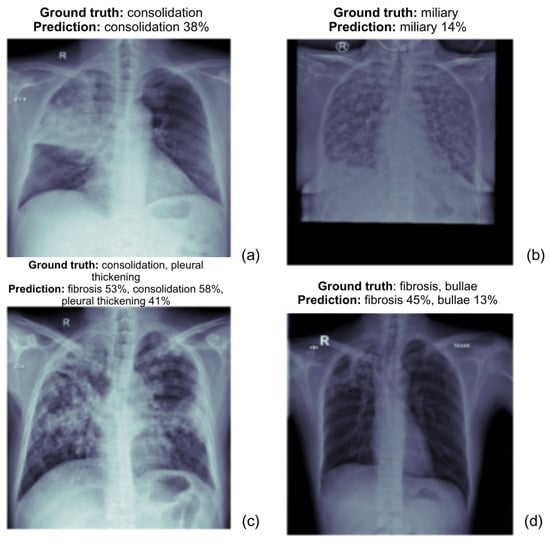

Below, as shown in the Figure 6, are the prediction results of the ViT Base model, demonstrating its ability to classify normal and tuberculosis (TB) anomalies in chest X-rays. Each label is accompanied by a confidence score, highlighting the model’s certainty for each predicted abnormality.

(a)

The actual diagnosis is consolidation, and the model predicts it with 38% confidence.

(b)

The actual diagnosis is miliary tuberculosis and the model predicts miliary TB with 14% confidence.

(c)

The ground truth includes consolidation, fibrosis, and pleural thickening. The model predicts these with fibrosis 53%, consolidation 58%, and pleural thickening 41%, all of which align closely with the actual diagnosis.

(d)

The actual diagnosis is fibrosis and bullae, and the model predicts fibrosis with 45% confidence and bullae with 13%. The prediction covers both conditions but is less confident about bullae.